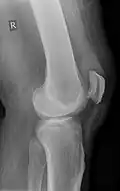

X-ray of a tear of the patellar tendon. On the left: The kneecap is pulled up. On the right: Significant dent in the soft tissue above the kneecap. -